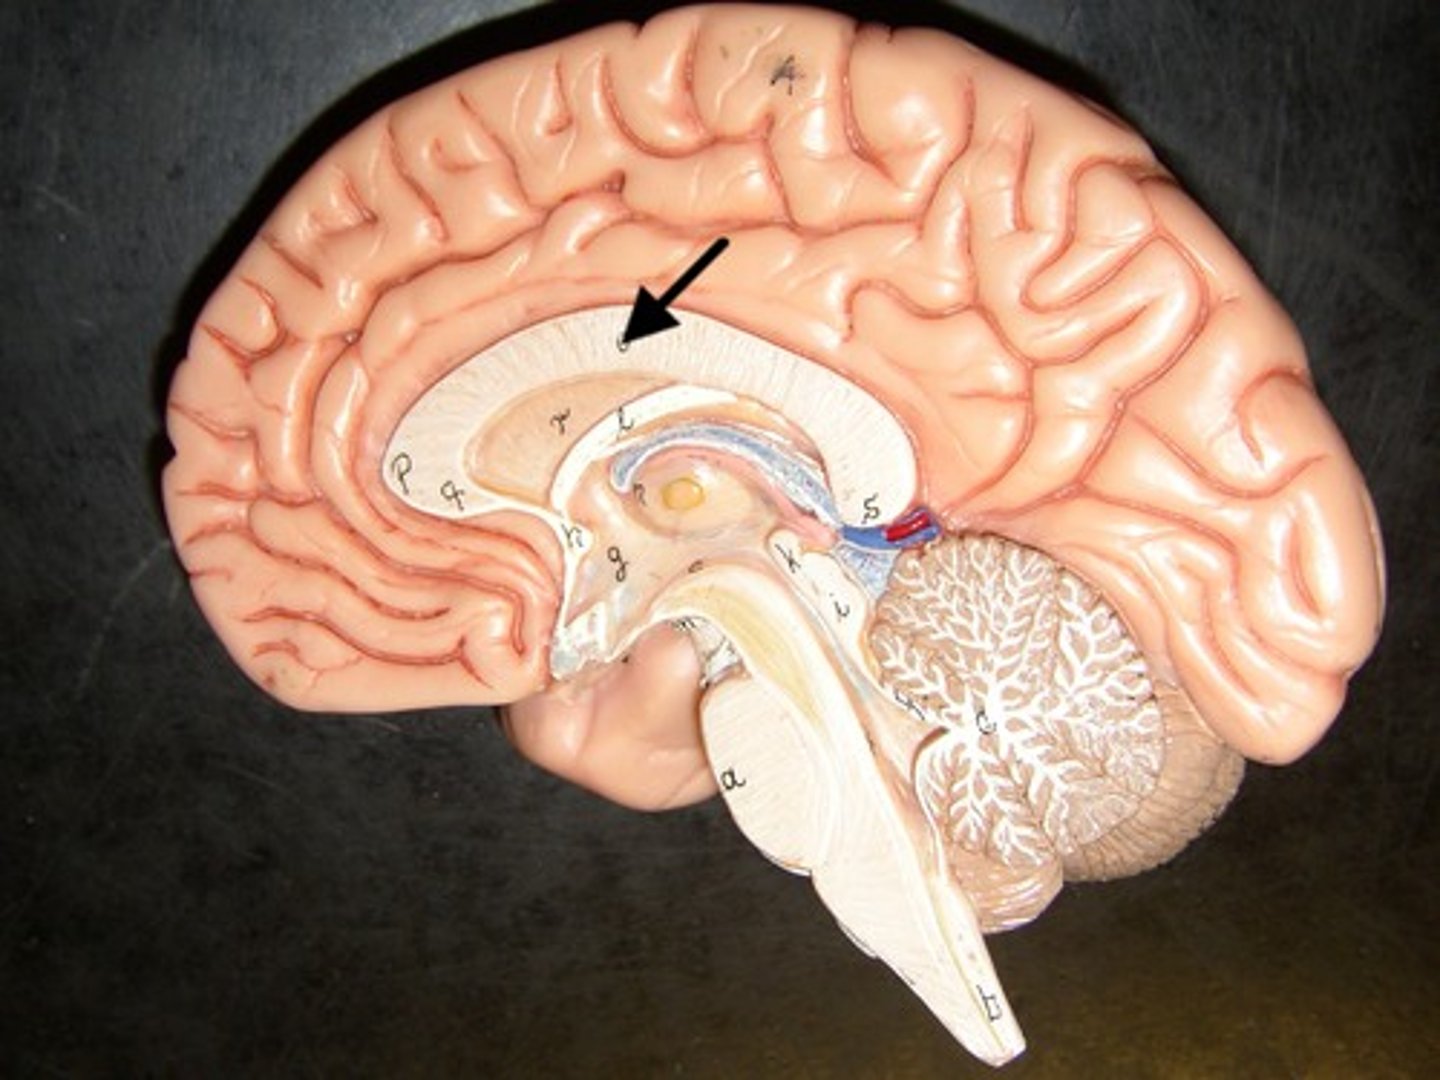

cingulate gyrus

plays role in expressing emotions via gestures and resolves mental conflict

corpus callosum

A thick band of axons that connects the two cerebral hemispheres and acts as a communication link between them.